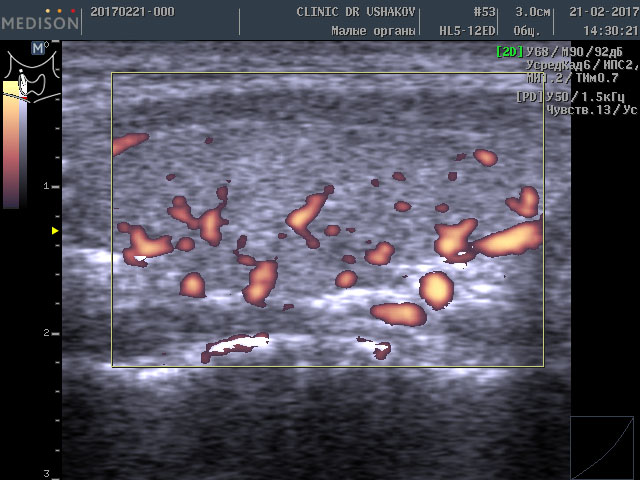

Ошибочно думать, что при таком сильно выраженном дефиците щитовидных гормонов (Т3 и Т4) щитовидная железа ослаблена и её «функция снижена». Ультразвуковое исследование показало, что объём железы почти нормальный 12,7 мл (даже немного индивидуально увеличен), а кровоток значительно усилен (рис. 5 и 6). Сравните насыщенность кровотока (по выраженности красных участков) с приведенными ранее примерами.

Рисунки 5 и 6. Пациентка К., 45 лет, левая и правая доли щитовидной железы в режиме ЭДК. Кровоток (обозначен красным цветом) в значительной степени усилен (Такое состояние сосудистой сети характерно для гипертиреоза ― повышения функции щитовидной железы»).

Заметно более выраженное кровообращение, которое прямо указывает на соответствующую значительную нервную стимуляцию ткани железы и её сосудов (одновременное сильное влияние со стороны нервных центров на ткань железы и кровоток). Это признак очень интенсивного перенапряжения щитовидной железы. Именно такая картина наблюдается при УЗИ в случае гипертиреоза ― избыточной продукции гормонов щитовидной железой, т.е. состоянии, которое называется врачами «повышение функции щитовидной железы». Это доказывает, что гипотиреоз ― усиление функционального напряжения щитовидной железы (Под влиянием ТТГ и нервных стимулов щитовидная железа избыточно и значительно перенапрягается для обеспечения организма достаточным количеством гормонов, потребление которых увеличивается при неблагоприятных условиях; только в нашей Клинике дано пояснение усилению кровотока в ЩЖ при гипотиреозе).